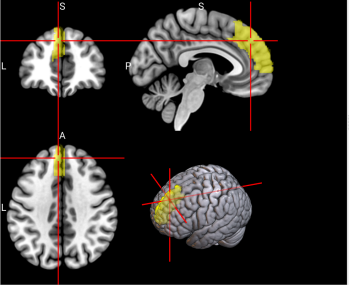

4

L Superior frontal gyrus, dorsolateral (SFG)

Left superior frontal gyrus is involved in working memory, spatial processing and other higher cognitive processes [59].

/word/media/image8.png/word/media/image8.png